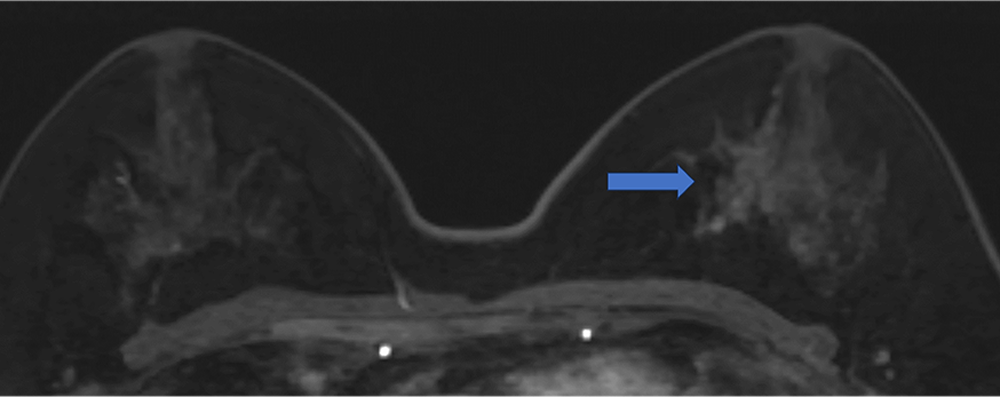

5. Ultrafast DCE 造影剤投与約20秒後、23秒後、26秒後

BPEが目立たないため、左乳房内側の病変が容易に同定できる

ultrafast MRI 造影剤投与

約23秒後

約26秒後